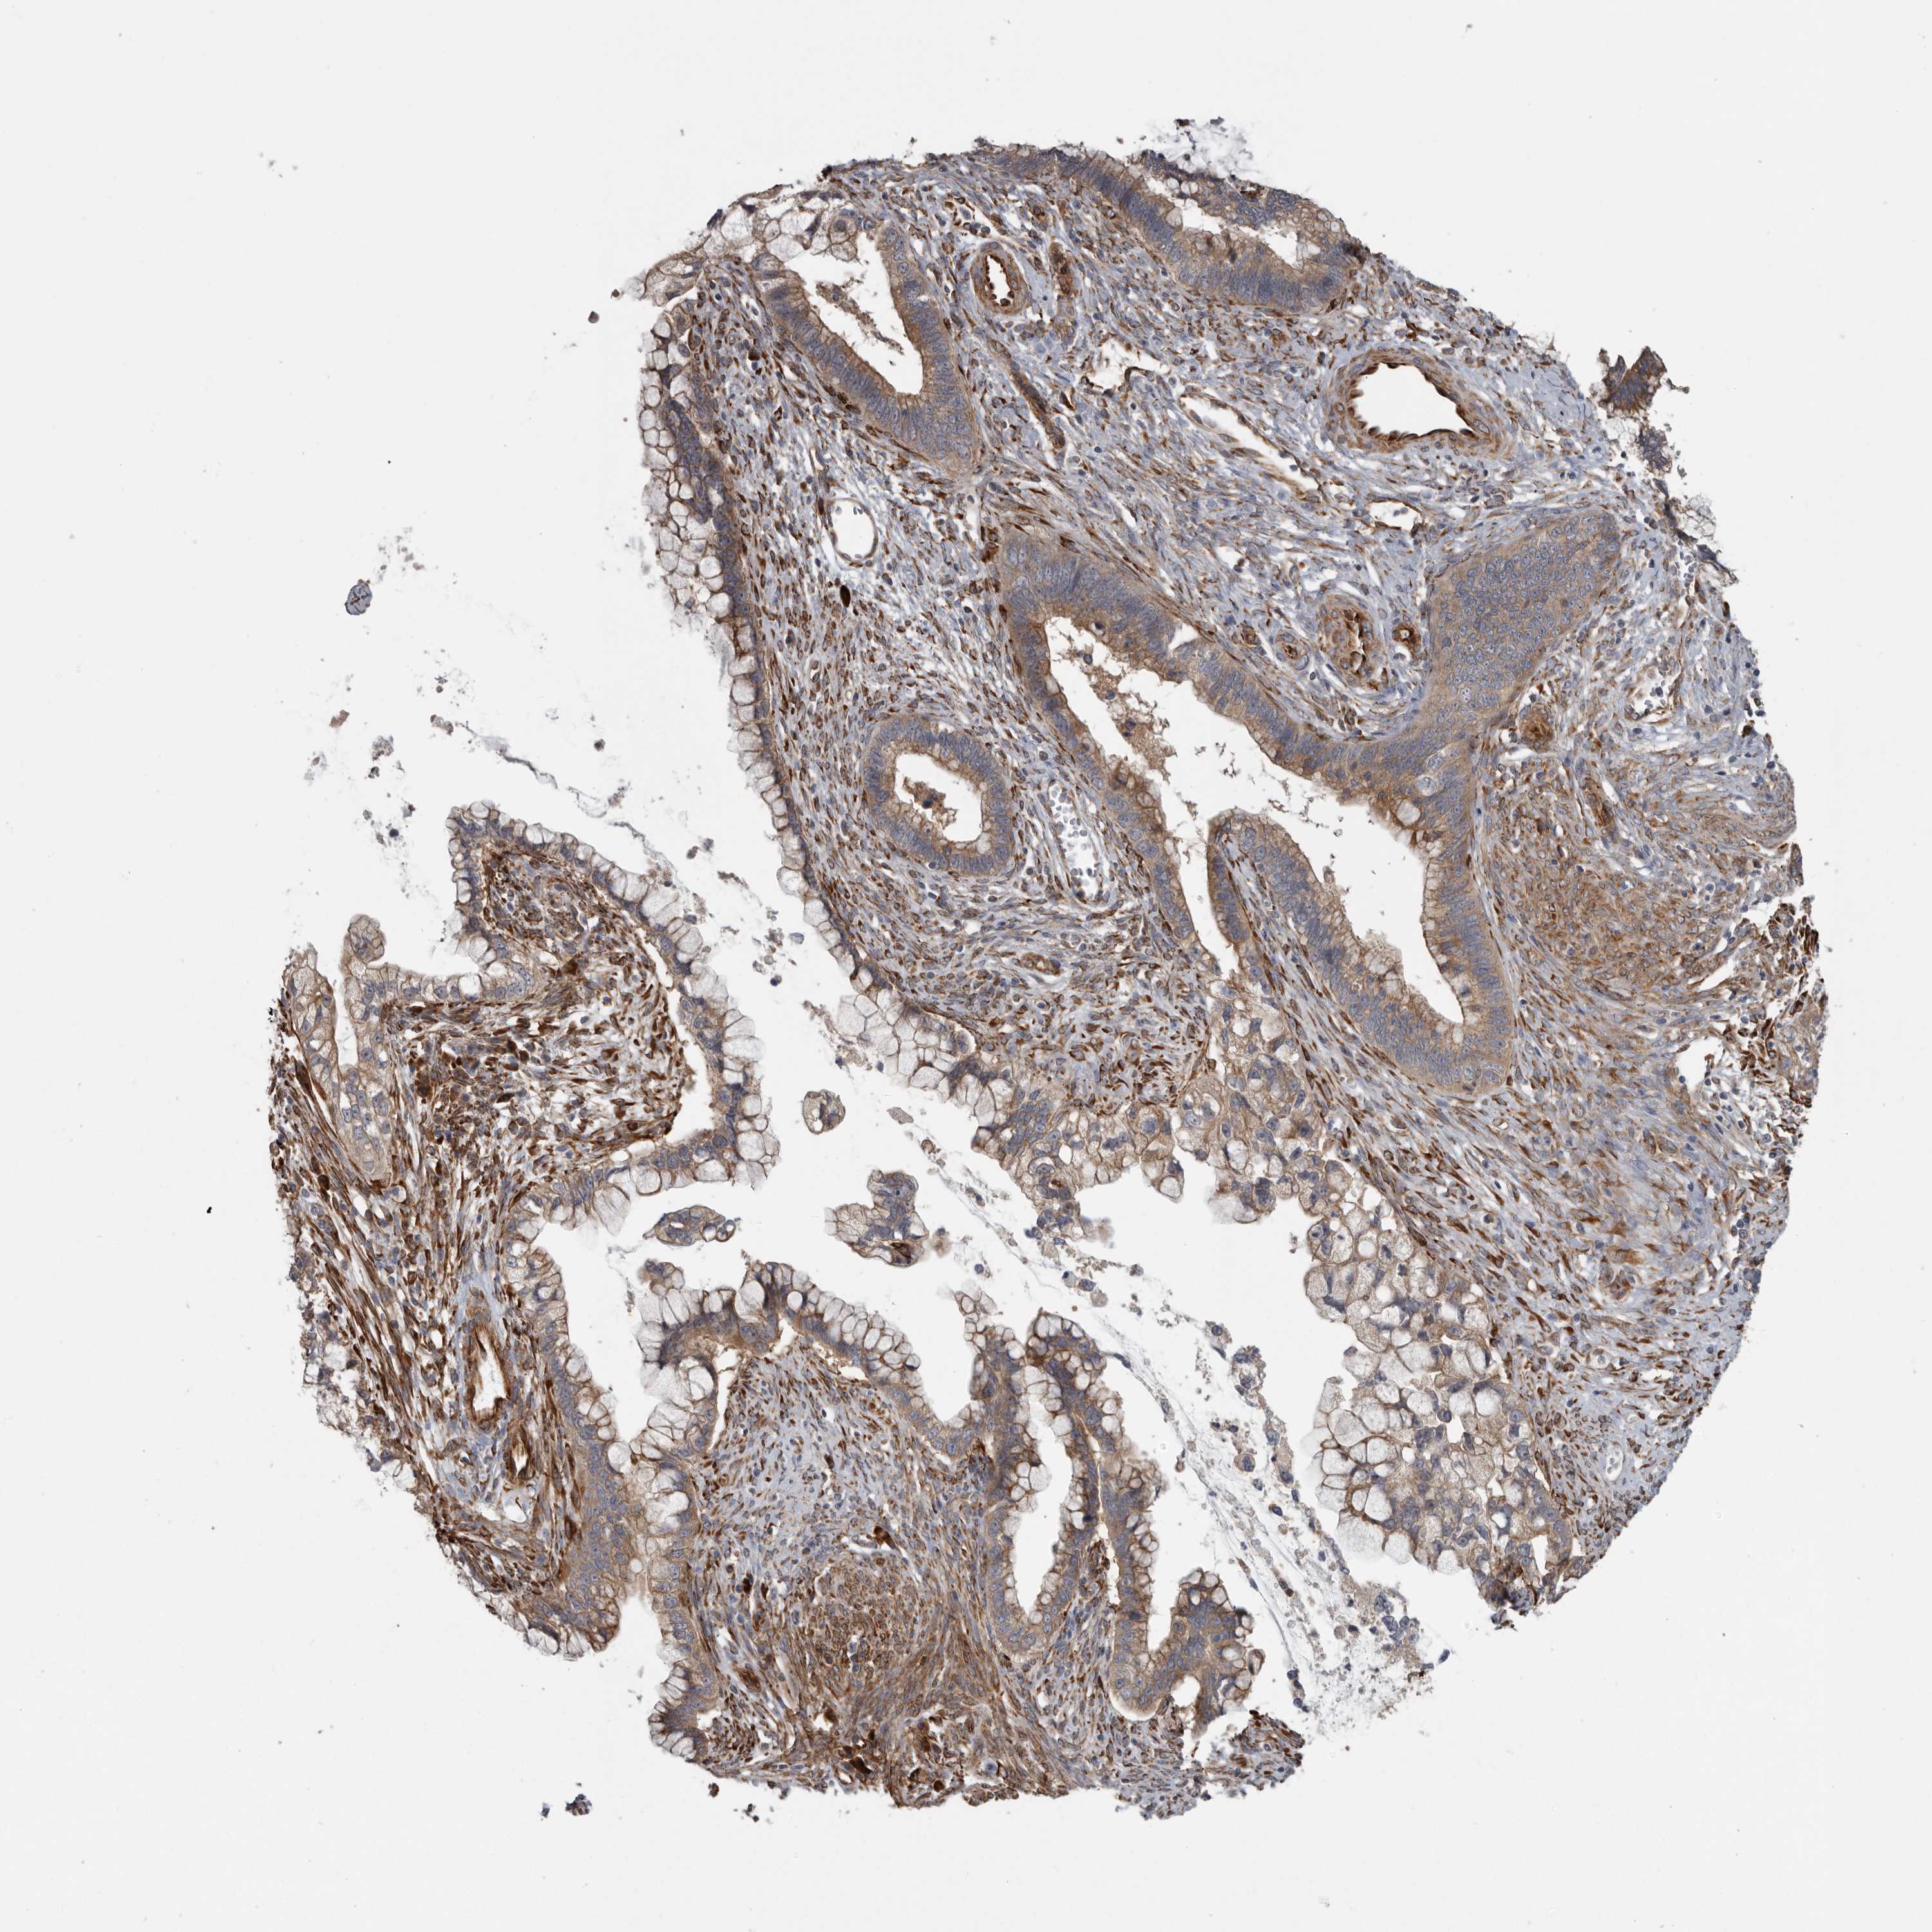

CERVICAL CANCER - Protein expressioni

A mouse-over function shows sample information and annotation data. Click on an image to view it in a full screen mode. Samples can be filtered based on level of antibody staining by selecting one or several of the following categories: high, medium, low and not detected. The assay and annotation is described here.

Antibody stainingi

Antibody staining in the annotated cell types in the current human tissue is reported as not detected, low, medium, or high, based on conventional immunohistochemistry profiling in selected tissues. This score is based on the combination of the staining intensity and fraction of stained cells.

Each image is clickable and will lead to virtual microscopy that enables deeper exploration of all samples and also displays staining intensity scores, fraction scores and subcellular localization as well as patient and tissue information for each sample.

Antibody HPA028357

Adenocarcinoma, NOS